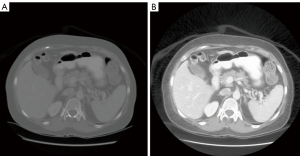

where v is the old gray-scale value that is mapped into the new gray-scale value h; cdfmin is the minimum non-zero value of the CDF; M × N is the image size; and L is the number of new gray levels. Figure 2 compares a CT scan image before and after equalization. We found that applying image equalization improved the model performance significantly, as it made images from various sources more comparable.